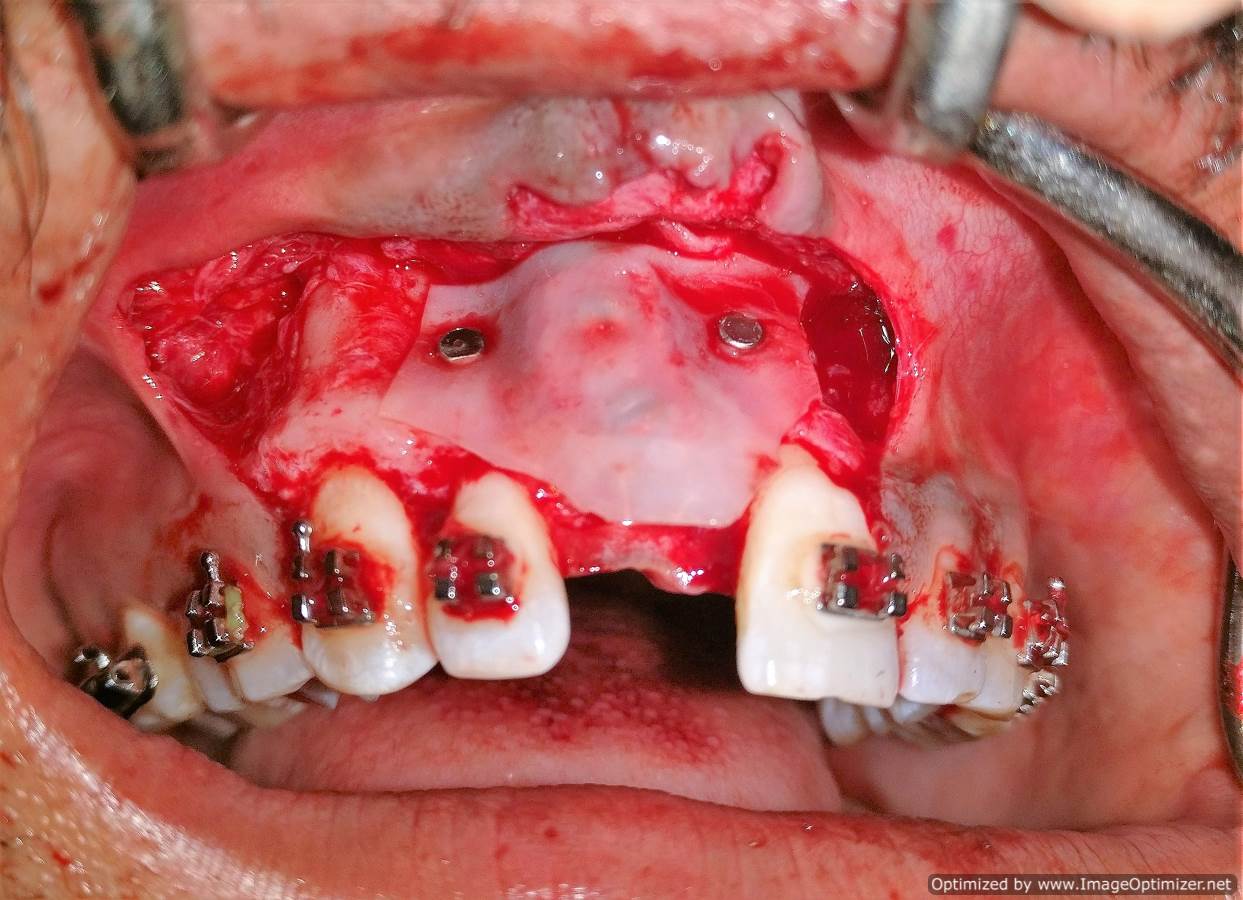

Dental Implant Case Report -03

Home / Case Report / Implant / Dental Implant Case Report -03